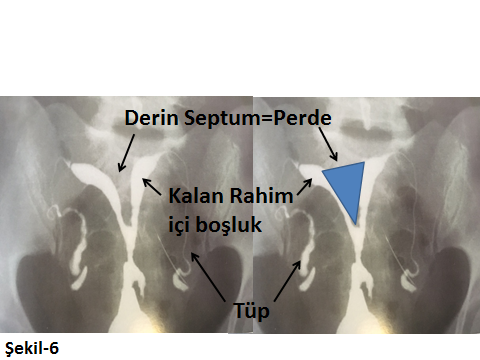

Rahimin normaldeki görünümü üçgen alanına benzeyen bir yapıdır. Bu yapıda doğuştan olan ya da sonradan ortaya çıkabilecek bozukluklar ve bunların dereceleri büyük bir doğrulukla belirlenebilir. Örnek olarak rahim içinde bir Septum yani Perde durumu var ise ufalmış rahim içi boşluğuna bağlı gebe kalamama ya da gebe kalıp tekrarlayan düşükler yaşayan bir kadında sorun Histeroskopik operasyon ile tüme yakın çözülebilmektedir.

Aşağıda farklı HSG görüntüleri ile konu görsel hale getirilmeye çalışılmıştır.

Rahimin doğuştan farklı görüntülerde şekil bozuklukları olabilir. Bunlar derecesine göre, infertiliteye ya da tekrarlayan düşüklere neden olabilirler.

Şekil-5’te normalde üçgen olan rahim içi yapısında var olan çöküklük ya da halk arasında perde olarak da adlandırılan septum görülmektedir. Bu perde (septum), farklı olgularda farklı derinliklerde olabilir. Bu perdeye bağlı olarak da gebeliğin yerleşebileceği normal rahim içi boşluğu farklı darlıklar gösterebilir. Şekil-6,derin bir perde durumunun HSG görüntüsüdür. Bu görüntülerden de fark edileceği gibi rahimin perdeden etkilenmeyen ve beyaz renkte görülen rahim içi alanı çok daralmış olduğu için gebeliğin bu kısıtlı sahalarda büyümesi zor ya da imkansız hale gelecektir.

Bugün bu sorun, çok kısa bir Operatif Histeroskopi yaklaşımı ile düzeltilebilmekte ve kişi normal üçgen rahim içi görünümüne sahip olabilmektedir.